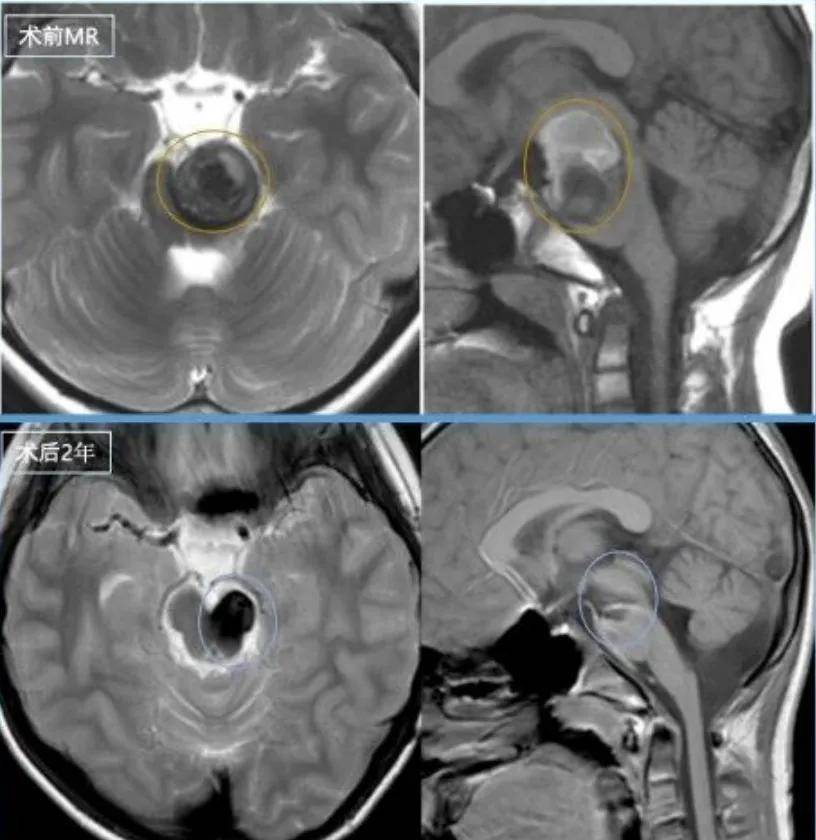

术前情况脑干脑桥偏左侧占位,锥体束受压迫,见含铁血黄素环。

术后三年复查显示无复发

目前术后三年复查显示无复发。额部淡淡疤痕成为男孩勇敢的勋章,他恢复了往日活泼爱笑的性格,但这段经历为他的笑容增添了超越年龄的坚毅。